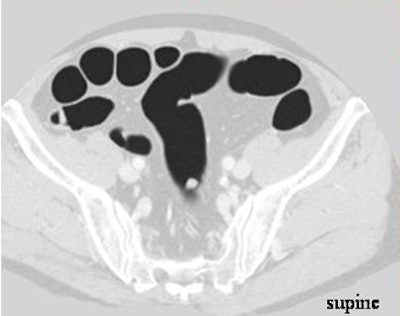

| Above, sessile 7-mm polyp in sigmoid colon of 60-year-old man. Virtual 3D views of supine (left) and prone (right) datasets show a small sessile polyp (arrow) in the sigmoid colon. Below, transverse 2D CT colonographic images of supine and prone (not shown) datasets also show the polyp (arrow) in the sigmoid colon. Bottom, conventional colonoscopic findings confirm the presence of the lesion (arrow). Biopsy was subsequently performed, and the final pathologic diagnosis was of an adenomatous polyp. Images courtesy of Dr. Se Hyung Kim. |